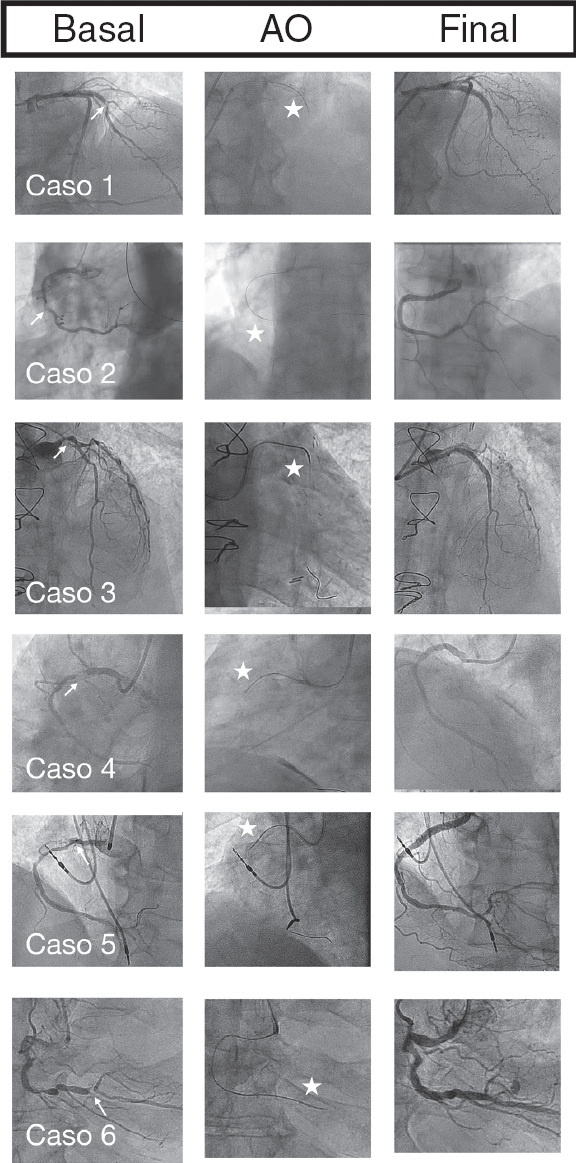

En todos nuestros casos tuvo éxito la AO, con cruce de la corona a través de la lesión que permitió posteriormente la angioplastia sin complicaciones mayores. En la figura 1 se ofrece un resumen con las imágenes angiográficas de cada caso.

Figura 1. Coronariografía basal, aterectomía orbitacional (AO) y coronariografía final. Las flechas señalan la lesión no cruzable, y las estrellas, la corona de la AO.